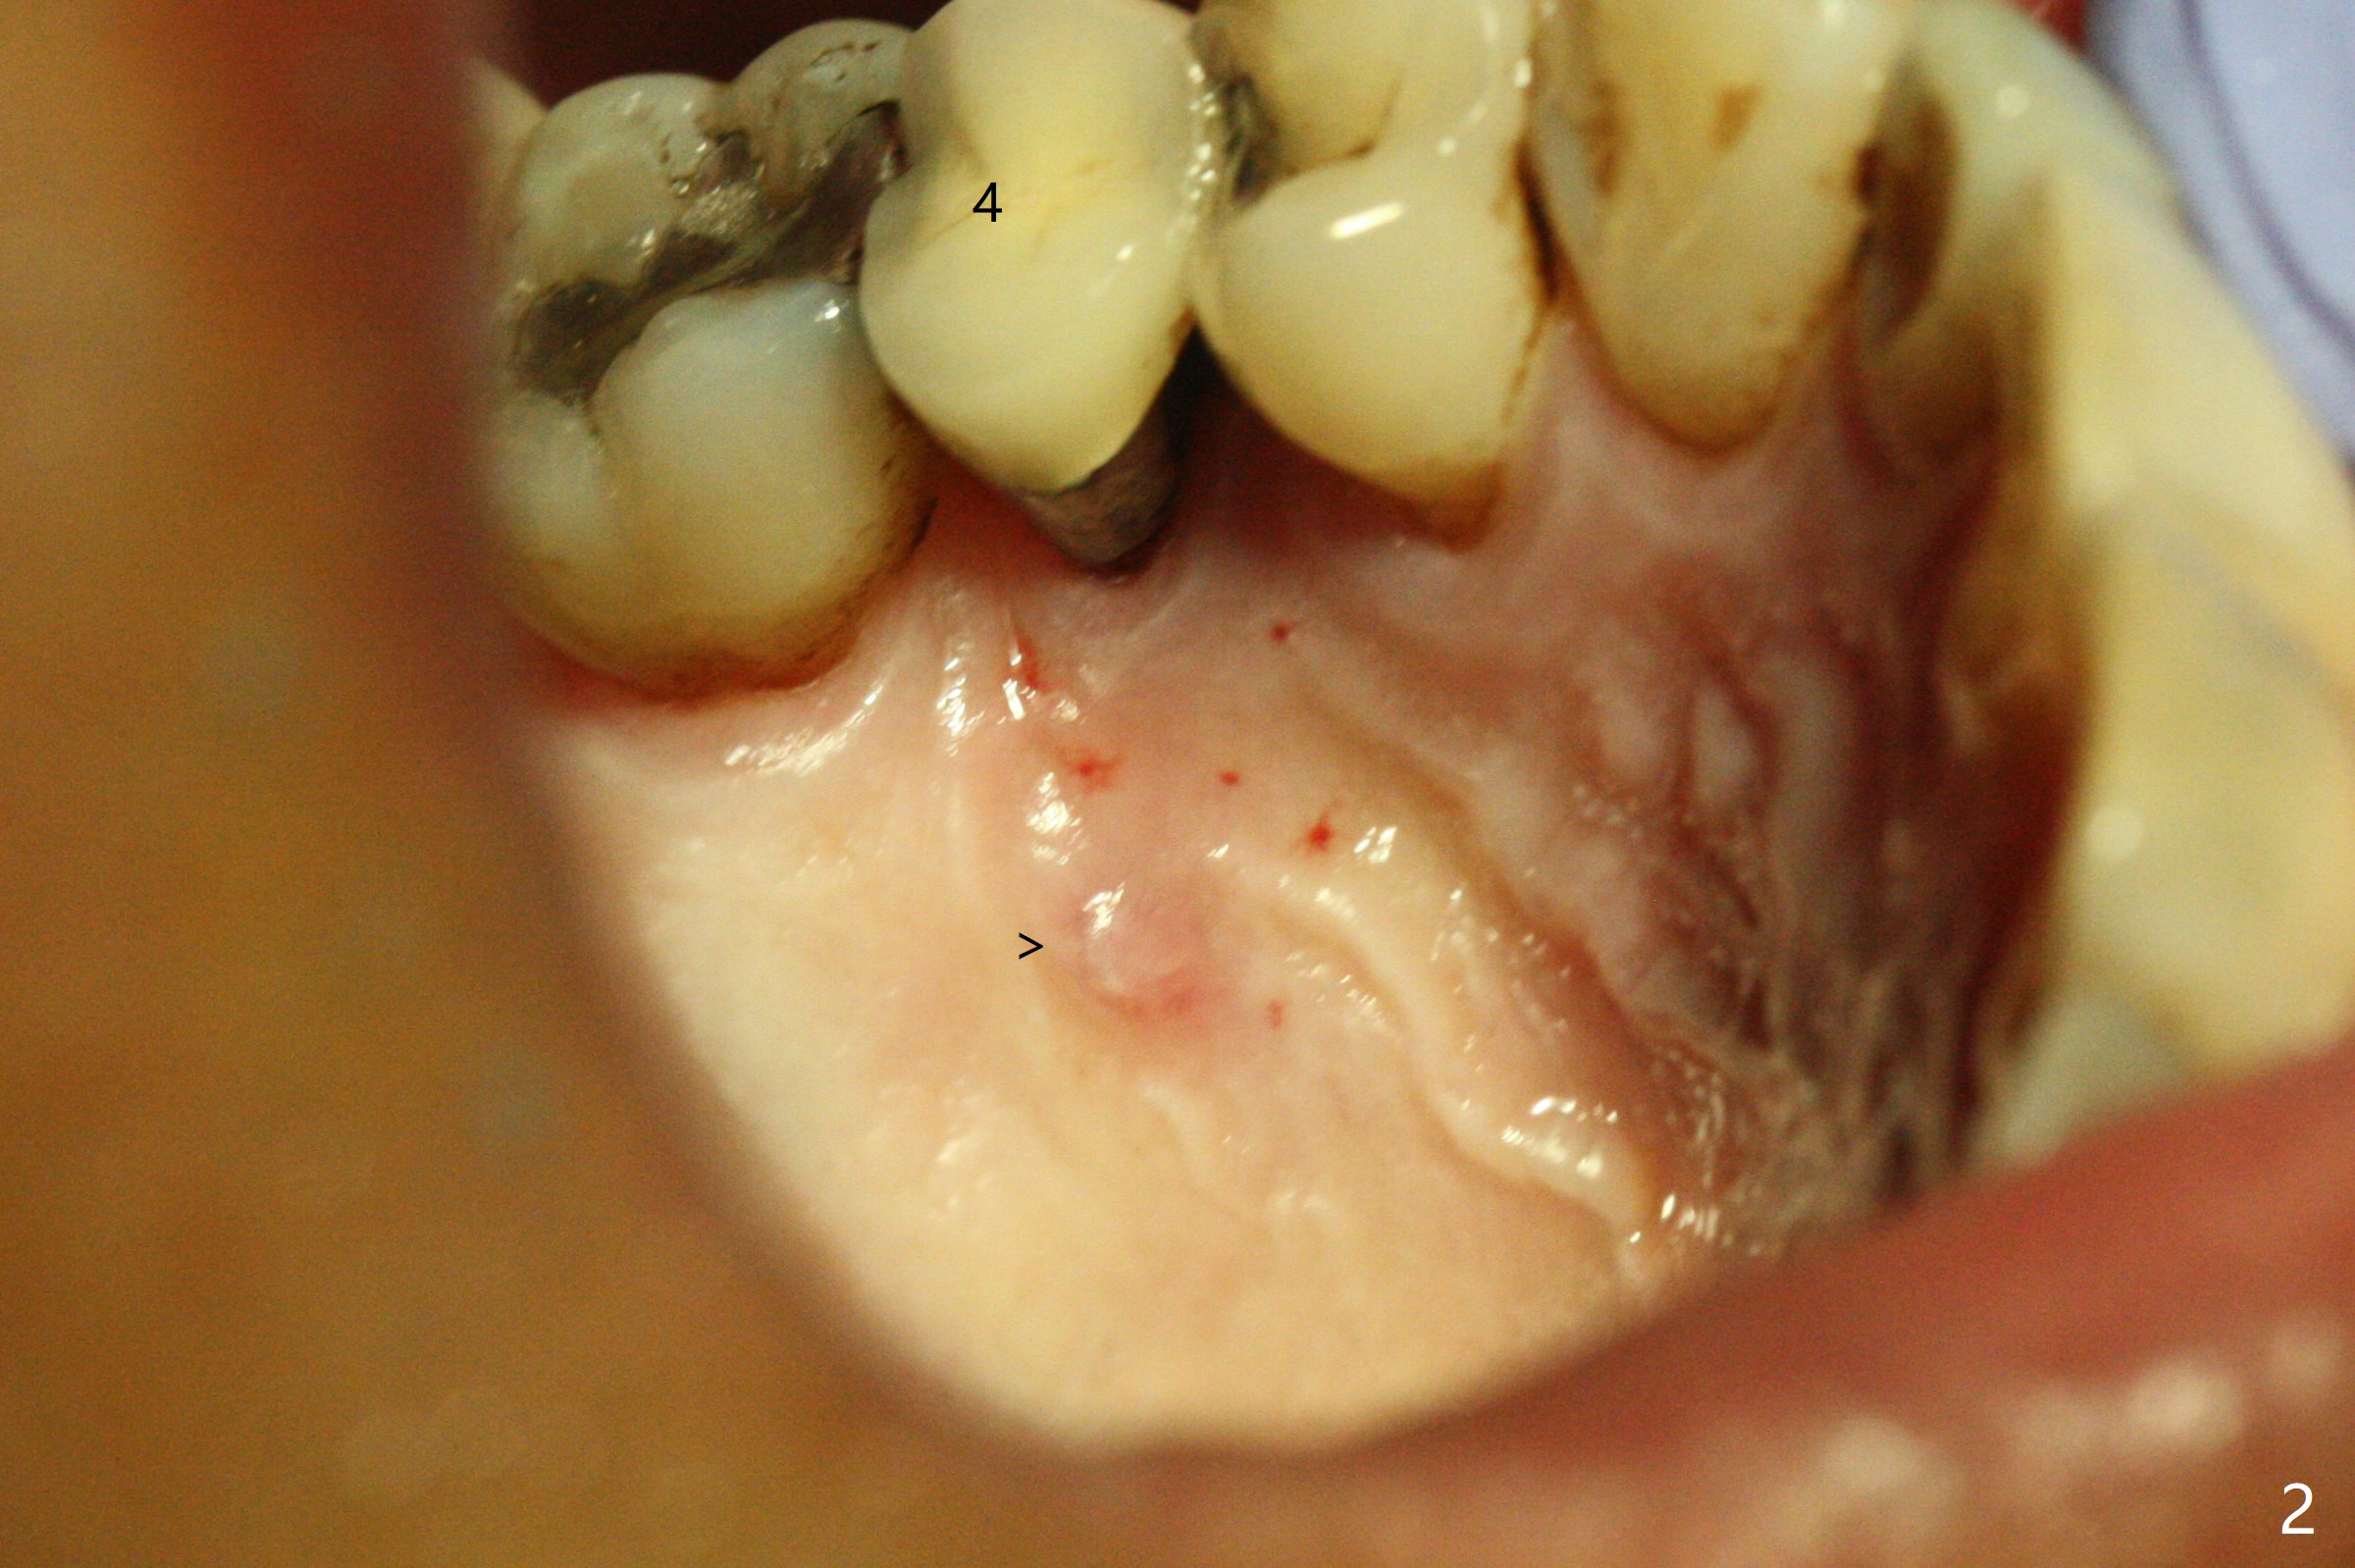

The 48-year-old man agrees to extract the tooth #4 with buccal and palatal fistulae (Fig.1,2 >) and large PARL (Fig.3 *) because of purulent discharge. The large post (Fig.3 P) is most likely associated with a longitudinal fracture. The latter is not noted until postop (Fig.4 <). Intraop finding is large amount of granulation tissue removed from the mesial apical region (Fig.3,5 *). With 10.5 mm offset, Sinus Approach Drill (19 mm) is estimated too short for sinus lift after 3x8.5 mm drill. Without careful repeated check, 2.2x10 and 2.2x11.5 mm drills are used. The sinus floor is perforated, but the membrane seems to be intact. The perforation is too small to insert PRF, but alright for allograft. Then nose blowing test shows that the sinus membrane is perforated, which seems to be repaired after placement of 2 pieces of PRF membrane, followed by another round of allograft (Fig.5 G), which is lifted by a 4x10 mm IS dummy implant. Before placement of a 4.5x11.5 mm final UF implant, allograft is placed in the 3 defective bony areas mentioned above, including the apical mesial one (Fig.6 *). But the final UF implant seems too short with non-satisfactory torque. The latter appears to be solved with the increased length of the implant (Fig.7). The gingiva around the provisional (P) is healthy without fistulae buccal (Fig.8) or palatal 17 days postop (Fig.9). A new abutment with 1 mm longer cuff is seated completely 5.5 months postop (Fig.10 < (no gap), as compared to Fig.7). The lower portion of the mesial defect seems to have been repaired (Fig.11 arrow, as compared to Fig.7). The bone in the sinus seems stable 1.5 years postop (Fig.12). There is no crestal bone loss 4 months post cementation (Fig.13). Return to Upper Premolar Immediate Implant, Trajectory II Xin Wei, DDS, PhD, MS 1st edition 09/27/2019, last revision 04/12/2021